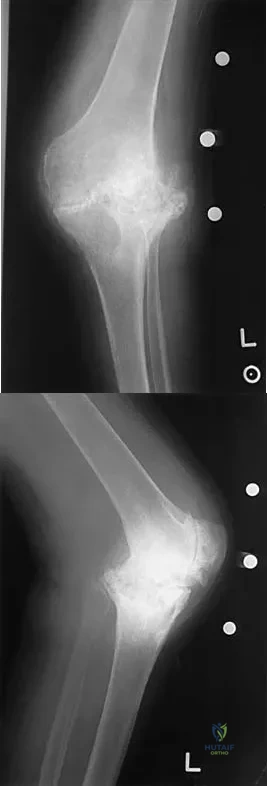

Question 80

A healthy, active, independent 74-year-old woman fell and sustained the elbow injury shown in Figures 41a and 41b. Management should consist of